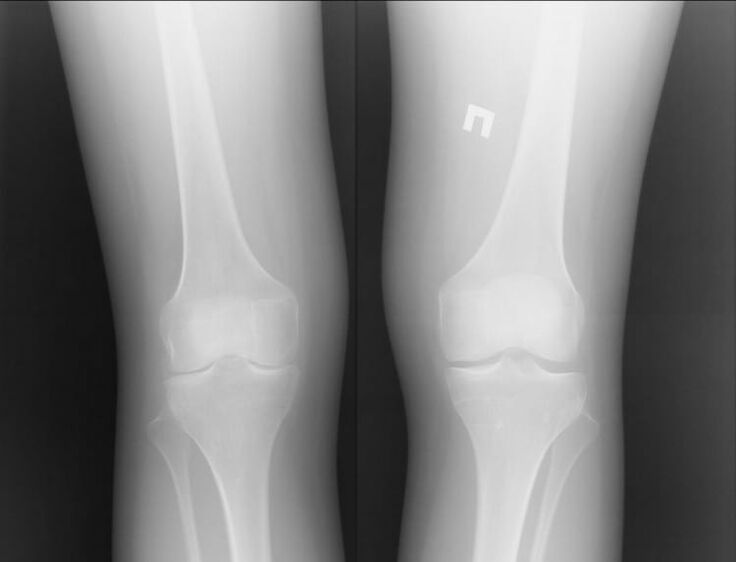

Of course, both diseases are very serious and it is difficult to say which is worse.However, we can consider the example of a problem in the knee joint.Patients with arthritis, i.e. inflammatory processes, can be helped.

Most often this occurs due to other infections in the human body.When they are healed and the joint inflammation is eliminated, knee osteoarthritis no longer bothers you.

Osteoarthritis is a completely different story.This is a separate disease that is caused by problems in the cartilage tissue.This is often not possible without surgical intervention.This is followed by another long recovery process.

Therefore, we can say that osteoarthritis is a more serious disease.However, arthritis can cause the first disease.Both complaints should not be neglected.It is better to contact a specialist immediately.